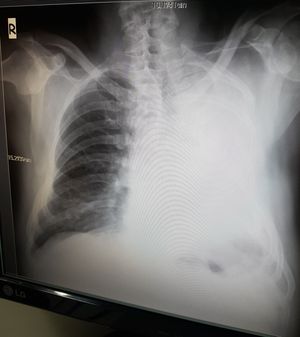

A patient without a left lung.

Deviation of trachea to the white out part is more often related to lung obstruction or might be atelectasis ! And patient is not without a lung ..

(Surgery with lung taken)